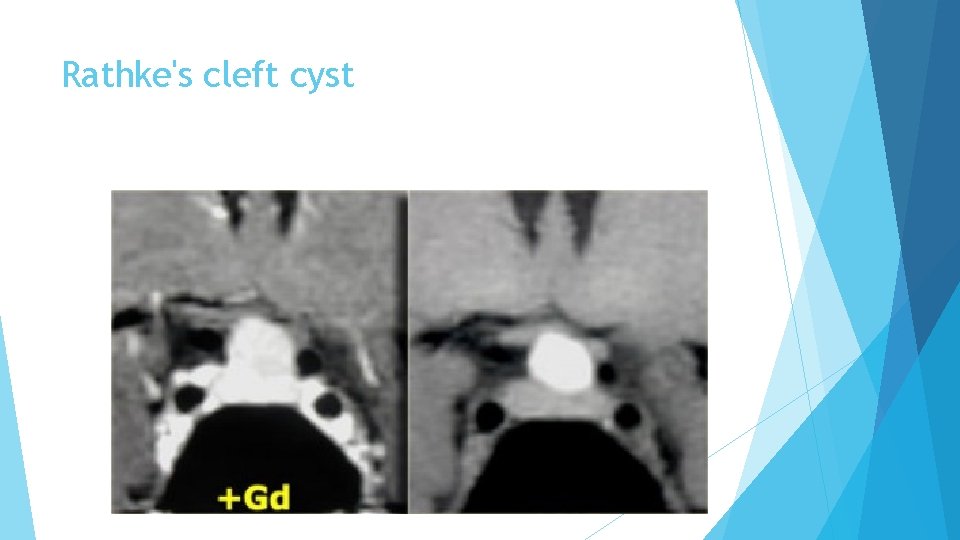

Rathke's cleft cyst is the second of three pathologies derived from Rathke's cleft epithelium. The cyst is fluid-filled and has very thin walls with a thickness of only one or two cell layers. These walls can contain cells which secrete fluid, allowing the cyst to grow and compress adjacent structures. Rathke's cleft cysts can occur either in or above the sella turcica.

Rathke's cleft cyst